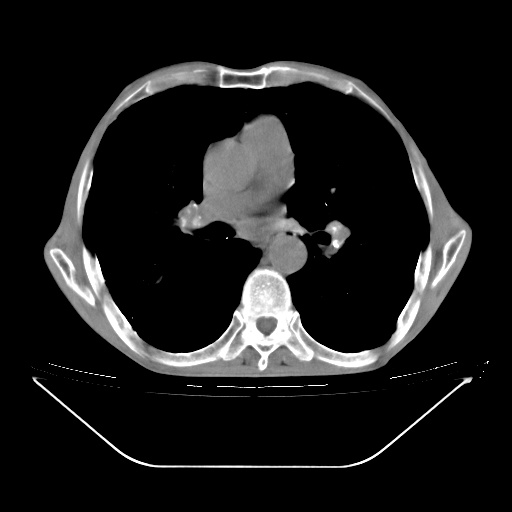

以下是引用zsl6918在2008-8-25 21:55:00的发言:[br]符合右肺周围性肺癌并肺内转移,左肺结核球。双肺肺气肿。腰椎附件转移。

以下是引用随光逐影在2008-8-25 22:03:00的发言:[br]1)考虑右肺下叶周围性肺癌并肺内转移,腰椎附件转移。2)左上肺结核(结核球形成)。3)双肺肺气肿(多发肺大泡形成)。4)双肺门区及纵隔内多发淋巴结钙化。